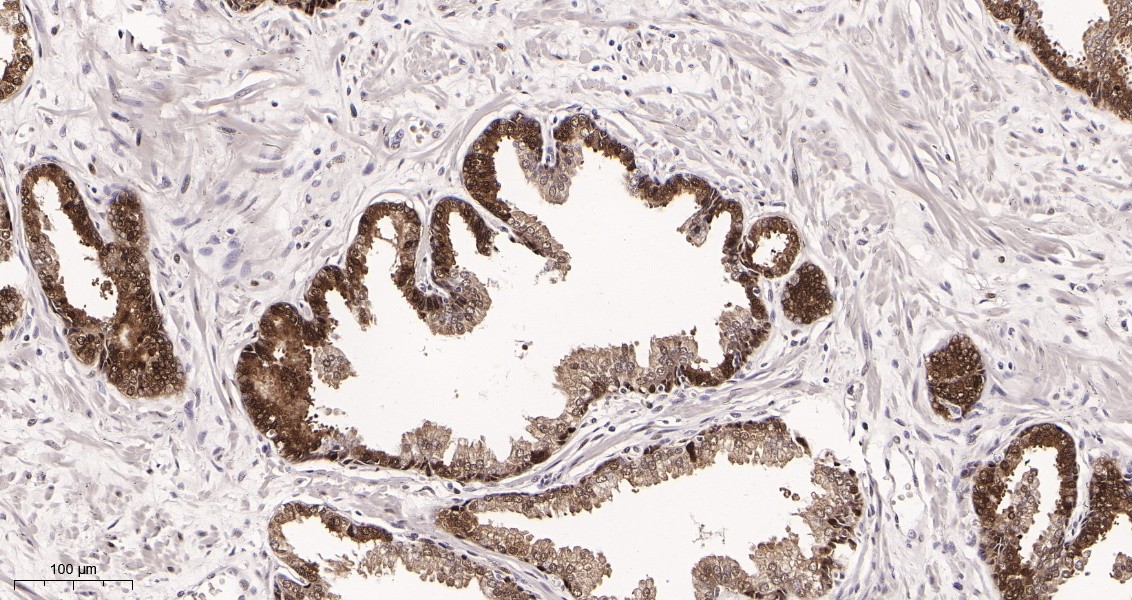

Immunohistochemical analysis of paraffin-embedded Human prostate tissue. 1, primary Antibody was diluted at 1:200(4~C,overnight). 2, EDTA pH 9.0 was used for antibody retrieval(>98~C,20min). 3,Secondary antibody was diluted at 1:200(room tempeRature, 30min).